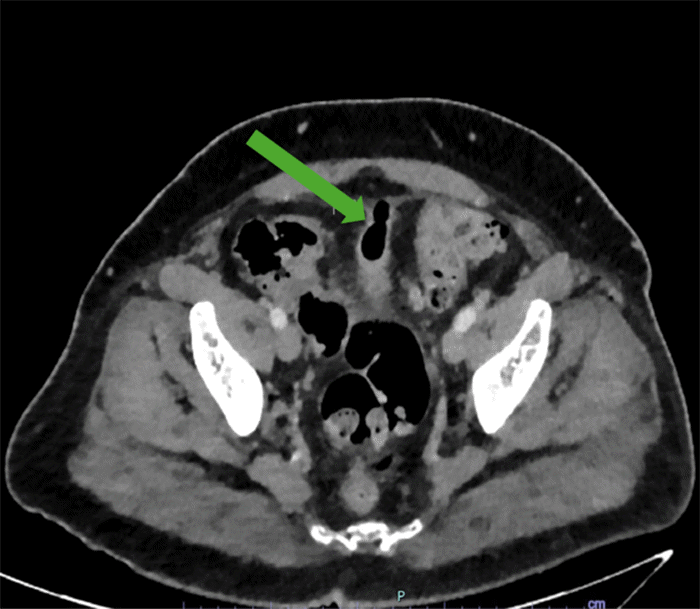

Initial evaluation via computed tomography (CT) of the abdomen and pelvis identified findings consistent with acute-on-chronic diverticulitis of the mid-sigmoid colon, without evidence of abscess or frank perforation. A mass-like inflammatory appearance at the dome of the bladder suggested a colo-vesical fistula, although a definitive fistulous communication between the inflamed colon and the bladder was not unequivocally visualized. Additionally, a prominent midline gas-filled outpouching was noted extending superiorly from the bladder dome into the prevesicular extraperitoneal space, consistent with a urachal remnant or diverticulum (Figure 1). The patient was diagnosed with a urinary tract infection and complicated diverticulitis and was discharged with a 10-day course of antibiotics, with referrals for outpatient follow-up with colorectal surgery and urology.

Figure 1. CT Demonstrating Urachal Remnant. Published with Permission

Axial CT scan of the pelvis. The image shows a gas-filled outpouching (green arrow) arising from the dome of the bladder and extending superiorly into the prevesicular extraperitoneal space, consistent with a urachal remnant